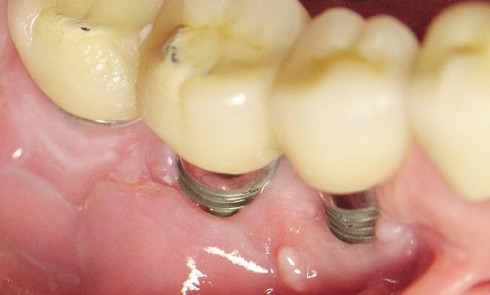

Article réservé à nos abonnés La cicatrisation péri-implantaire : de l’ostéointégration à la ré-ostéointégration ?

L’utilisation des implants pour remplacer les dents absentes est une méthode de référence, avec un bon résultat à long terme,...